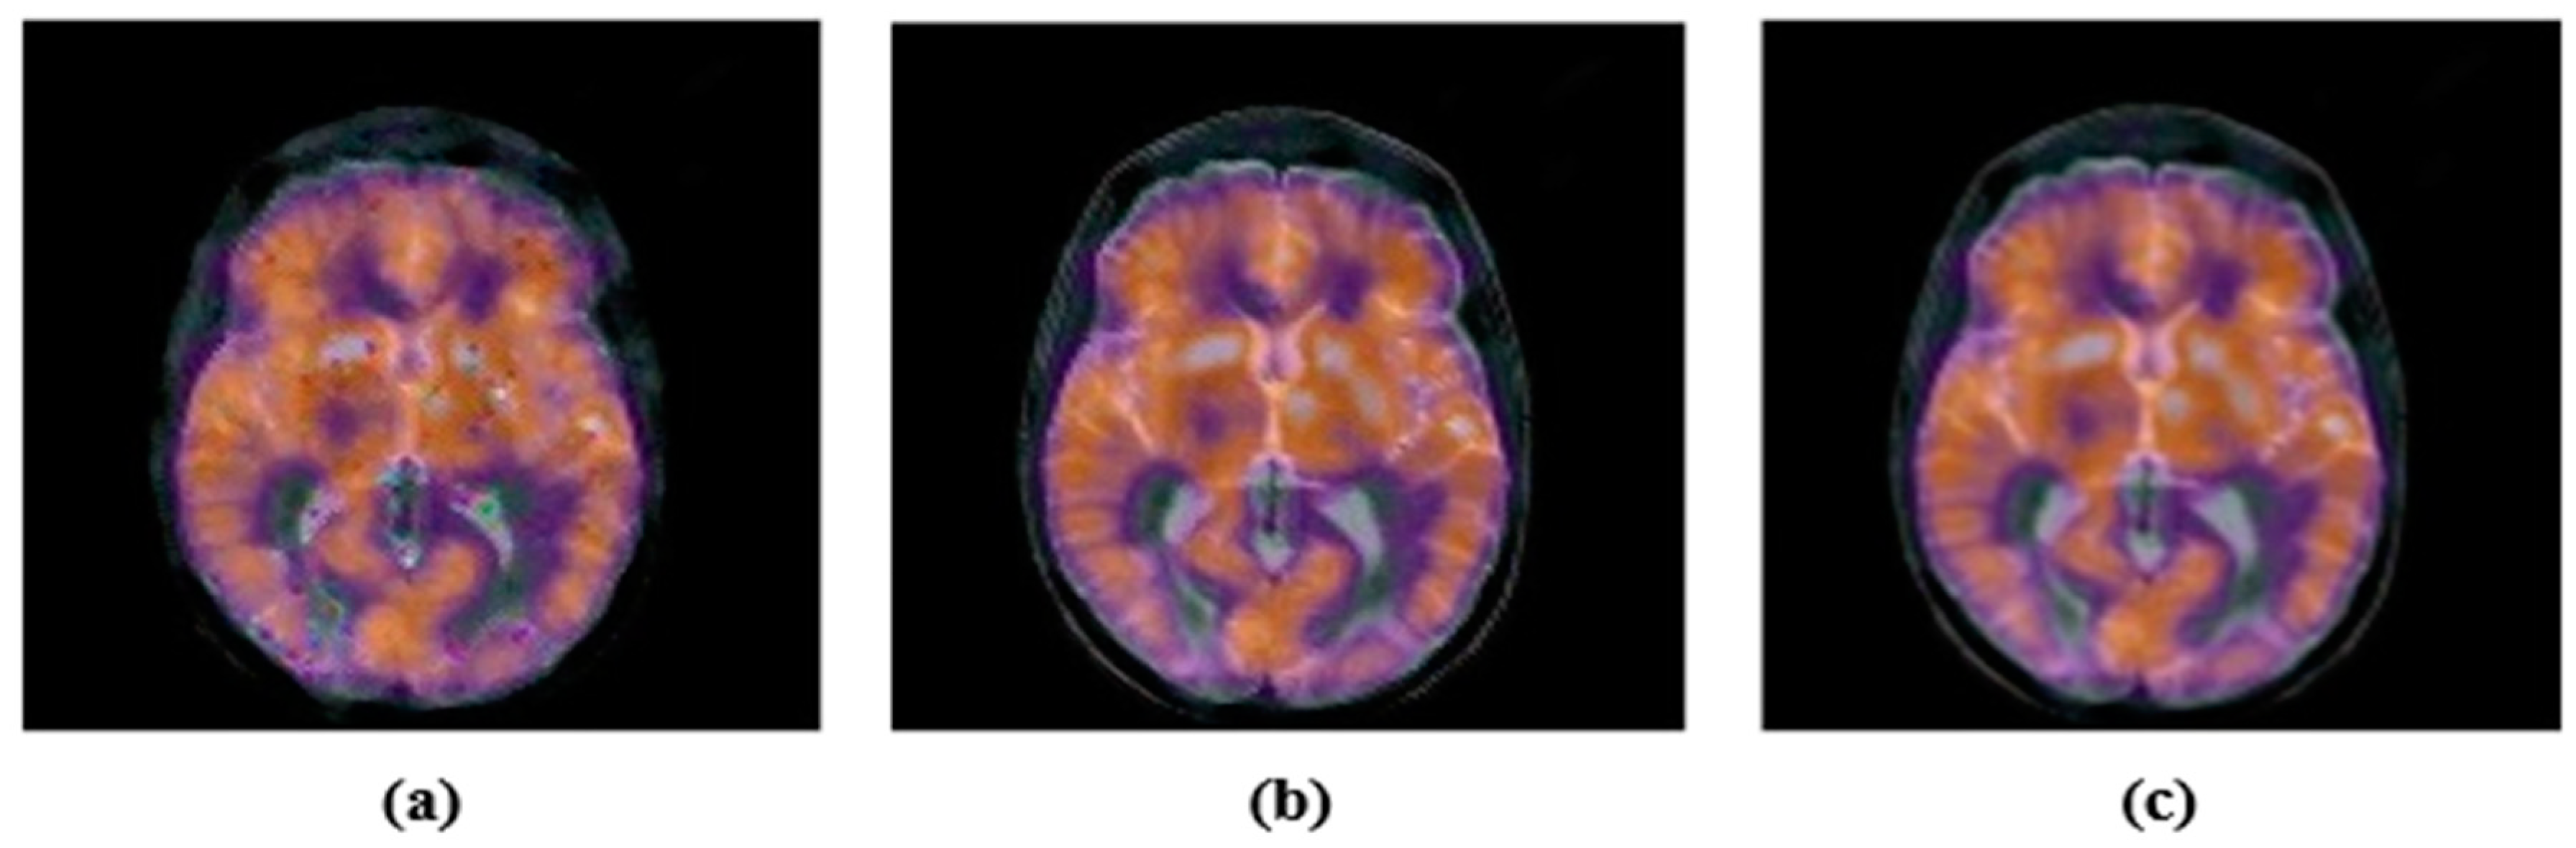

4.3. Robustness Comparison with Similar Algorithms